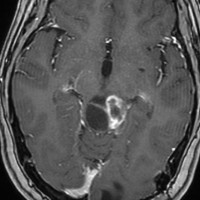

毛様細胞性星細胞腫であり,基本的には初回手術で全摘出できるのですが,現実的には,技術的に難しすぎるので部分摘出で終えることが多いでしょう。この子は,15歳の時に閉塞性水頭症のために,頭痛,嘔吐,意識障害,瞳孔不同となりました。開頭部分摘出術と第3脳室開窓術で回復して,その後にカルボプラチンとビンクリスチンの化学療法を受けました。

でも腫瘍増大が止められずに,発症1年後に54グレイ30分割の放射線治療を受けています。さらにその半年後くらいから再増大しましたが,スードプログレッションと考えられました。上左MRIは放射線治療前,上右MRIは放射線治療1年後です。毛様細胞性星細胞腫は放射線治療後に一過性増大(多くはのう胞性増大)することが多いです。

のう胞性拡大が止まらず,発症3年後にまた再開頭手術 (left occipital transtentorial approach) で亜全摘出しました。右は術後の画像です。初発時の最初の手術で亜全摘出あるいは全摘出 gross total removalできていればと思える例です。